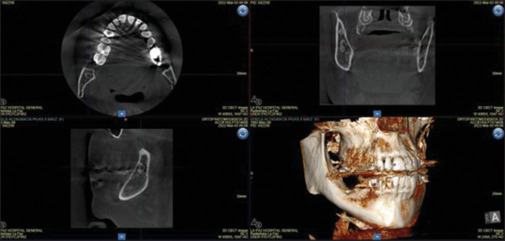

The anatomical location of certain lesions can be a difficulty when locating them intraoperatively. The use of surgical navigation allows anatomical structures to be located with great precision. However, there are technical difficulties with its use in mandibular surgery. Three-dimensional (3D) printing has established itself as a definitive tool in the generation of biomodels for diagnosis and treatment as well as implantable devices. Some applications, little explored today, have to do with the use of 3D-printed devices for the localization of hard-to-reach lesions. To determine the position of mandibular bone lesions, we propose using 3D printed localization guides manufactured "in-house," using freely licensed design programs (software) to design them, and made of biocompatible resins. This improves surgical precision and reduces morbidity from the intervention. 3D planning models are shown and segmented using open-source software (3D Slicer) using imported conventional computed tomography data. Digital component modification is possible with free software (Autodesk Meshmixer) to arrange precise osteotomy cuts for lesion localization. With the help of customized cutting guides, intraoperative placement is precise. These are created utilizing a fused filament manufacturing 3D printer and polylactic acid. Three localization guides were successfully completed, resulting in improved surgical accuracy and reduced surgical morbidity. The use of 3D surgical guides in cases of mandibular lesions in difficult or delicate locations saves the need for navigation, requires less surgical time, does not require splints or reference stars.